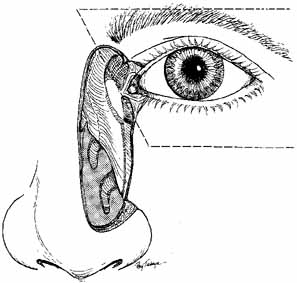

is aided by irrigation with 0.5 mL of an antibiotic steroid solution.  Fig. 19 Probing and irrigation of the nasolacrimal system. Hydraulic pressure is

used in an attempt to force fluid through the obstruction at the valve

of Hasner. If this attempt is unsuccessful, the cannula is slipped

down to the point of obstruction and pushed through gently but firmly. Dye

is injected from the syringe, and the patency of the system is confirmed

by suctioning the dye from the inferior meatus with a soft pediatric-size

plastic suction catheter. Fig. 19 Probing and irrigation of the nasolacrimal system. Hydraulic pressure is

used in an attempt to force fluid through the obstruction at the valve

of Hasner. If this attempt is unsuccessful, the cannula is slipped

down to the point of obstruction and pushed through gently but firmly. Dye

is injected from the syringe, and the patency of the system is confirmed

by suctioning the dye from the inferior meatus with a soft pediatric-size

plastic suction catheter.